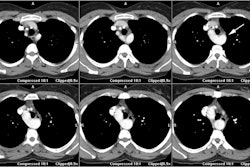

Coronary artery calcification: The patient below has a large calcification in their proximal LAD. Their total calcium score was 537. |